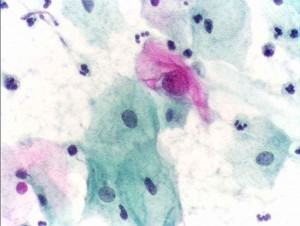

Il cancro alle ovaie e quello alla parete dell’utero potrebbero essere diagnosticati analizzando il materiale genetico presente nei campioni prelevati durante un semplice Pap test. Pap_testA suggerire le potenzialità di questa metodica, battezzata dai suoi ideatori PapGene test, è uno studio pilota coordinato da Luis Diaz, docente di oncologia alla Johns Hopkins University di Baltimora (Usa), i cui risultati sono stati pubblicati su Science Translational Medicine.

Attualmente il Pap test è utilizzato per rilevare la presenza di un eventuale cancro alla cervice uterina. La metodica prevede l’analisi al microscopio delle cellule presenti nel fluido cervicale. Quest’ultimo può, però, contenere anche cellule provenienti dalle ovaie e dall’endometrio, la parete dell’utero. Basandosi su questo dato di fatto Diaz e colleghi hanno pensato di utilizzare il sequenziamento del Dna per identificare la presenza di mutazioni associate a forme tumorali all’interno di queste cellule.